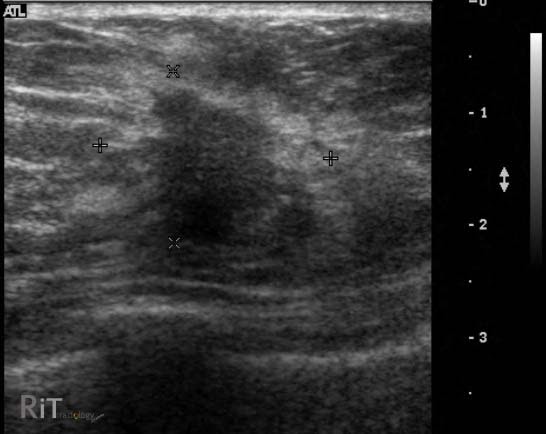

A diferencia de la tomografía computarizada, la resonancia magnética no utiliza radiación ionizante. En cambio, se basa en campos magnéticos y ondas de radio para crear imágenes detalladas de los tejidos internos. Durante la RM, el paciente se coloca en un tubo rodeado por un imán potente, lo que alinea los átomos en el cuerpo para crear imágenes de alta resolución.

La resonancia magnética es particularmente eficaz para visualizar tejidos blandos, articulaciones y órganos como el cerebro, el corazón y los vasos sanguíneos. La ausencia de radiación hace que la RM sea una opción preferida en situaciones donde se necesita evitar la exposición a rayos X, como en el caso de mujeres embarazadas o pacientes pediátricos.